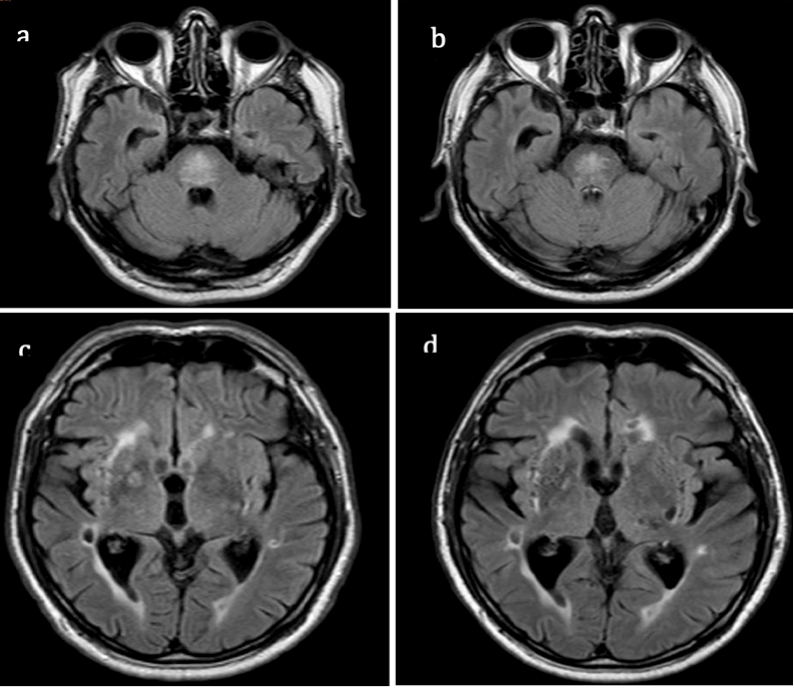

We cannot entirely exclude a neurodegenerative origin of the parkinsonian features observed or vascular parkinsonism. The latter is not consistent with our findings because of the slow progression of the same syndrome which is asymmetric parkinsonism without additional signs. Moreover, the lesions in deep nuclei remained stable over time (Figure 2). ODS and idiopathic Parkinson’s disease (PD) could be independently present in our patient, but it has been postulated that pontine myelinolysis may act as a trigger of a neurodegenerative process [7]; this may be the case for our patient. Of note, the patient had no other non-motor symptoms typical of PD, i.e., sleep disturbances and sensory disturbances, such as reduced olfactory perception, a typical and early symptom of this disease [8,9]. Furthermore, the 123I-MIBG documented findings are more likely compatible with parkinsonism than PD [10]. These data seem to make the hypothesis of a clinical case of parkinsonism, as opposed to one of PD, more plausible. Moreover, the late and progressive evolution could be linked to abnormal neuronal and synaptic network rearrangements associated with retrograde degeneration [5].

Figure 2. MRI fluid-attenuated inversion recovery (FLAIR) in 2007 (a,c) and in 2014 (b,d). During these years, there was a reduction in the volume of pontine myelinolysis (a,b); the hyperintensities in deep white matter and in deep nuclei are similar (c,d).